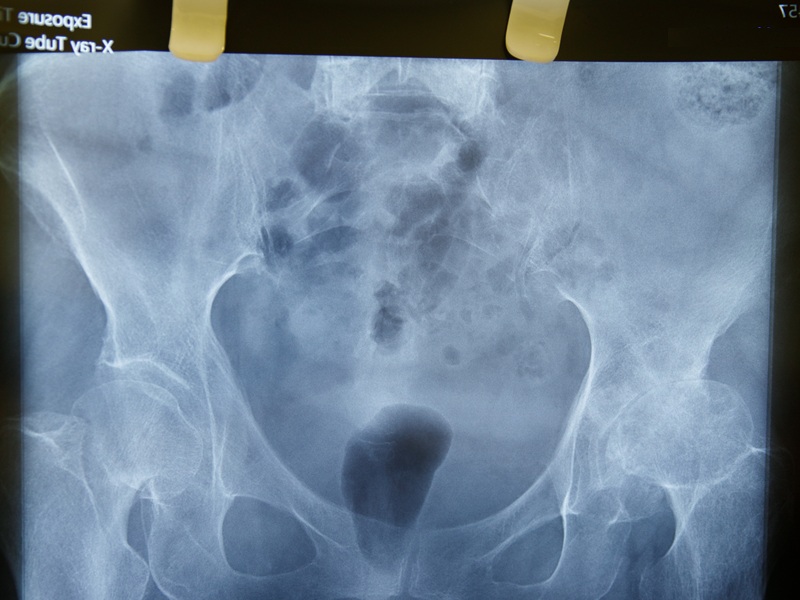

Комп'ютерна томографія стегна — це покрокове сканування нижньої кінцівки рентгенівськими променями з подальшим поєднанням окремих візуальних зрізів у єдине об'ємне цифрове зображення. За допомогою спеціального програмного забезпечення на комп'ютері можна обертати це 3D-зображення та оглядати досліджувані структури з різних ракурсів, з можливістю масштабування для детального розгляду. За необхідності отримання максимально деталізованих зображень застосовується контрастне підсилення, для якого попередньо вводиться препарат, що містить йод.

КТ стегна показує стегнову кістку, кульшовий суглоб, прилеглі кістки тазу, а також м'які тканини — м'язи, підшкірну клітковину та кровоносні судини. Відповідно, можна побачити їх патологічні зміни (запальні, дегенеративні), пошкодження, аномалії, новоутворення.